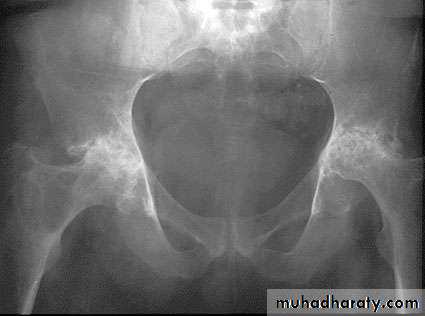

Changes are seen in the feet of diabetics with peripheral neuropathy.A vascular ( a septic ) necrosis :

Avascular necrosis , also known as osteonecrosis , is where there is death of bone due to interruption of the blood supply.The plain radiographic features including :

1. Increase density of the subchondral.

2. crescentic lucent line may be seen just beneath the articular cortex.

3.Articular cartilage space is preserved until degenerative changes super even .

4.In sub capital fracture of the femoral neck & fracture through the waist of the scaphoid bone , the femoral head & proximal pole of the scaphoid become fragmented & dense due to the ischemia .

MRI is imaging modality of choice for demonstrating a vascular necrosis and may show changes at time so early when radiograph may be normal .

A group of conditions , in which no associated cause for a vascular necrosis can be found . But the osteochondritis are now regarded as being due to impaired blood supply associated with repeated trauma .A-Perth's disease :

A vascular necrosis of the femoral head in children , is the most important example of the osteochondritis . the plain radiograph changes :

1.the earliest change is increase in density and flattening of the femoral epiphyses which later on progress to collapse & fragmentation.

2.epiphysis widened & consequently the femoral neck enlarge and may contain small cyst .

3.joint space is widened but the accetabulum not affected .

4.with healing, the femoral head reforms but remain permanently flattened & therefore responsible for OA in later life .